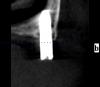

Wasja Опубликовано 10 декабря, 2012 Поделиться Опубликовано 10 декабря, 2012 Вот нарезка КТ Ссылка на комментарий

bullbull Опубликовано 27 марта, 2014 Поделиться Опубликовано 27 марта, 2014 Вот нарезка КТПри хорошем раскладе нижние простоят ещё несколько годков. А на счет верхних - сомневаюсь. Ссылка на комментарий